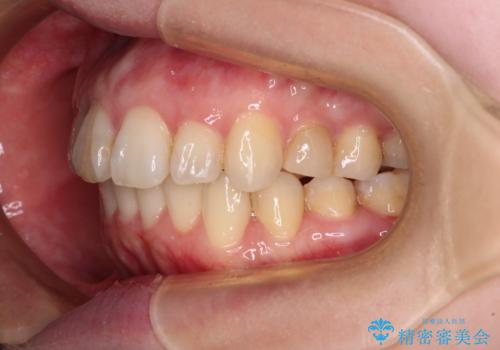

口元の閉じにくさを改善するためには、上顎臼歯を後方に移動させた咬み合わせにする必要があります。

インビザライン単体で改善することも可能ですが、達成する可能性が高くないため、カリエールディスタライザーという補助装置を併用して、より確実性を上げることとしました。

奥歯の咬み合わせを改善しながら、並行してインビザラインで歯列を整えることとしました。

カリエール・ディスタライザーを用いたことで上顎前歯の突出感はスムーズに解消され、歯列不正は1年半ほどでほぼ改善することができました。

しかし、その後インビザライン特有の奥歯がうまく噛めないという問題が長引き、改善に1年近い期間を要することとなりました。